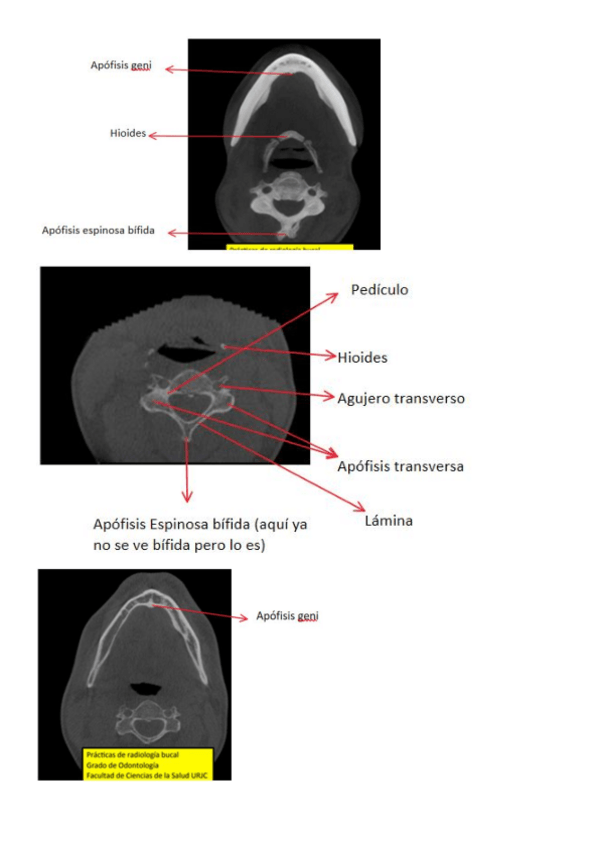

He publicado nuevos apuntes de 2º Radiología bucal: Practicas-CBCT.pdf

14 páginas